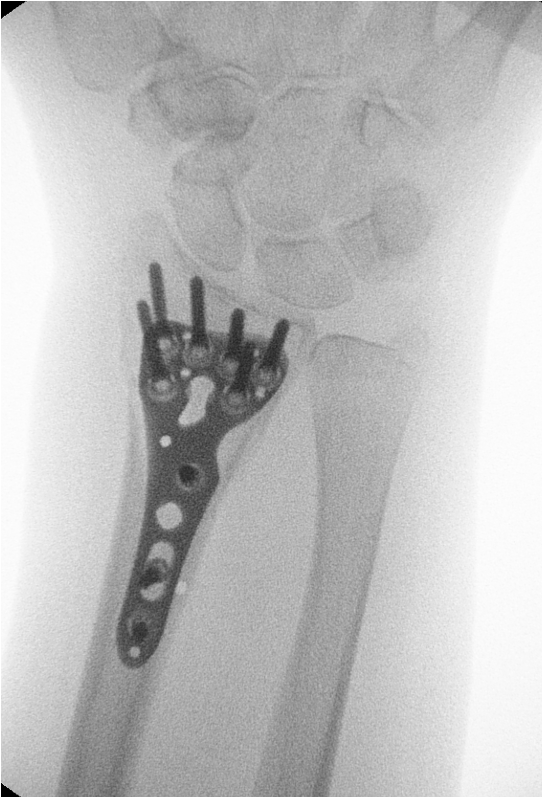

• Fracturas de muñeca

• Pseudoartrosis del escafoides (cuando la fractura no consolida correctamente)

• Inestabilidades ligamentosas de la muñeca (lesiones del ligamento escafolunar o lunopiramidal)

• Artrosis de la muñeca (postraumática, degenerativa o secundaria a lesiones previas)